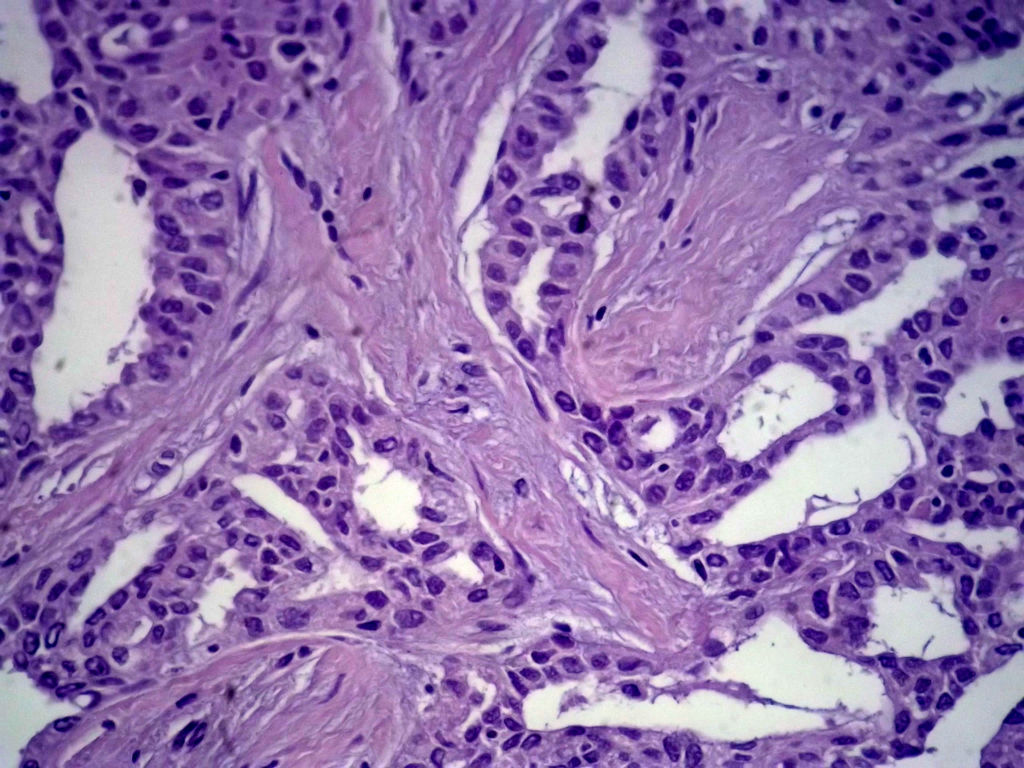

今天的一例术中冰冻。女,49岁,乳腺肿块。人气不旺,换个标题

腺病?癌?其他?(12楼常规,24楼免疫组化及会诊结果)图1

标签:浸润性导管癌 分泌癌 硬化性腺病

乳腺分泌型癌

1. Most likely no invasive cancer

2 Sclerosing adenosis

3 Ductal epithelial hyperplasia

4. Bundles d Smooth muscle?

导管是乎可见双层上皮,部分上皮增生并有一定异型,考虑硬化性腺病,待石蜡。

导管可见双层上皮,部分上皮增生并有一定异型,考虑硬化性腺病

腺体与腺体之间的对比差异太大,不放心,不除外是癌,如果是我的病例,再次取材冰冻

占楼传常规1-11为冰对。